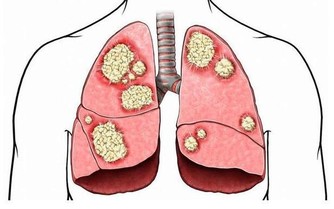

脂肪肝是指由於各種原因引起的肝細胞內脂肪堆積過多的病變,是一種常見的肝髒病理改變,而非一種獨立的疾病。